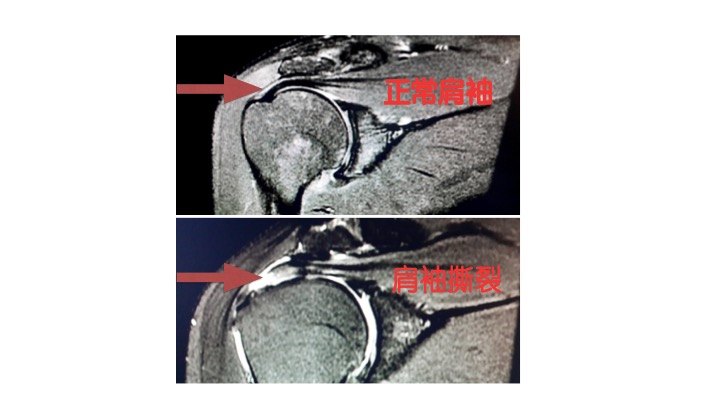

肩袖损伤

图片尺寸1060x778